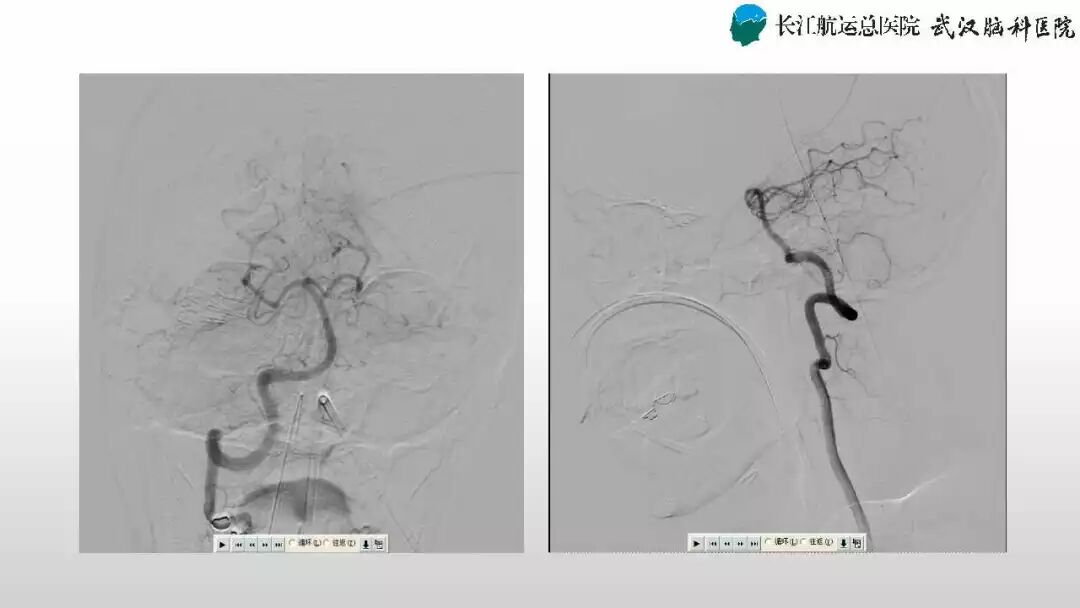

肖国民副主任医师:动静脉瘘手术